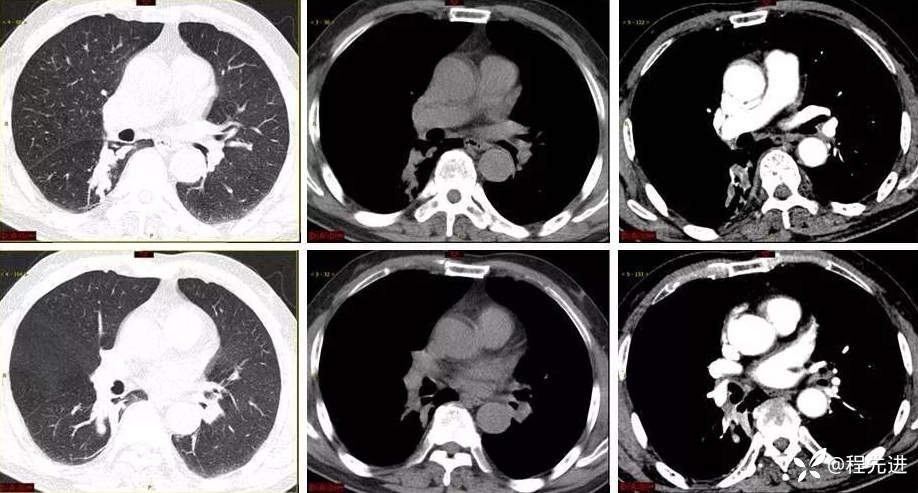

9月特别精彩病例|咳嗽伴咯血4月余,重点讨论胸部|结果已公布

患者性别:男

患者年龄:65岁

主诉:咳嗽伴咯血4月余

现病史:患者4月余前劳动后出现咳嗽,为阵发性干咳,以中午为主,后出现咯血,呈鲜红色,共5-6次,量最多时约50ml,约有3-4次。外院予以对症治疗(具体不详)后好转,1周前患者又出现咯血一次,约10ml。患者病程中无发热,时有胸闷,无胸痛,无呼吸困难,无盗汗,无恶心呕吐,无呕血黑便,食欲睡眠可,二便正常,体重无明显下降

凝血功能:D-二聚体0.69 mg/L(<0.55mg/L)

生化:钙2.13mmol/L(2.20-2.65mmol/L),白蛋白37.60g/L(40.0-55.0g/L)

C反应蛋白9.05 mg/L(0.0-8.0mg/L)

肿瘤标志物:神经原特异性烯醇化酶22.1ng/mL(<16.3ng/mL)